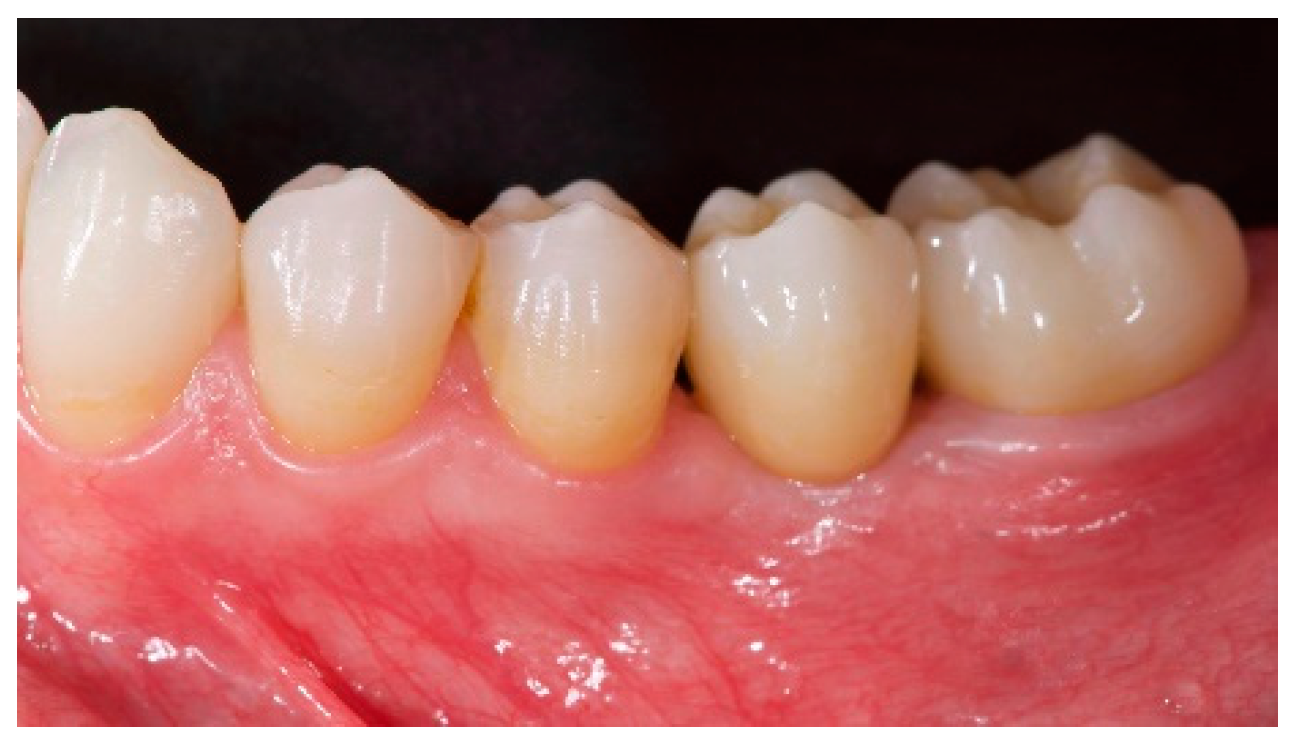

- The aesthetic evaluation was performed according to the pink aesthetic score (PES) on the vestibular and occlusal pictures taken including at least one adjacent tooth per side. The values were assessed at 6 and 12-months after loading follow-up examinations (18-months follow-up) [14] Seven variables (mesial papilla, distal papilla, soft-tissue level, soft-tissue contour, alveolar process deficiency, soft-tissue color and texture) were assessed with a 2-1-0 score (2 being best and 0 being poorest) by the same blinded dentist.